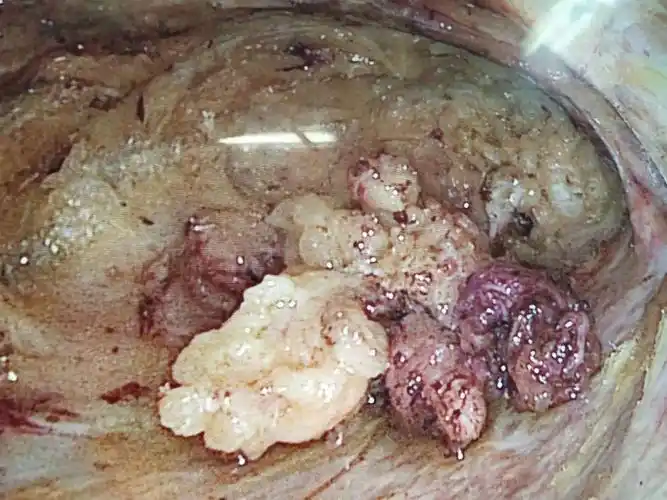

人乳头瘤病毒53型属于高危性hpv,长期感染可能引起女性宫颈,外阴或

带你深入了解女性癌症第二大杀手 宫颈癌

"外阴癌"都是拖出来的?

figo2021癌症报告外阴癌诊治指南解读